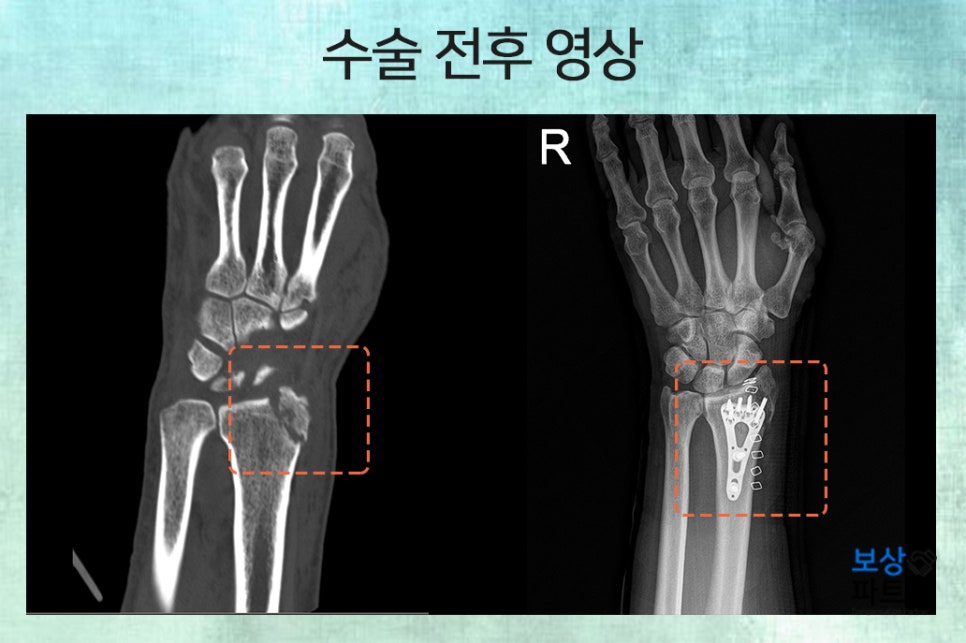

주상병은 요골 하단의 골절, 폐쇄성(S52520) 이었으며, 손목 부위의 관절을 침범한 골절이었습니다. 그래서 안정적인 고정 및 골유합을 위해 금속판과 나사를 넣는 고정술을 시행하였고, 향후 5~6개월 동안 장기간의 재활 및 통원 치료가 필요하였습니다.